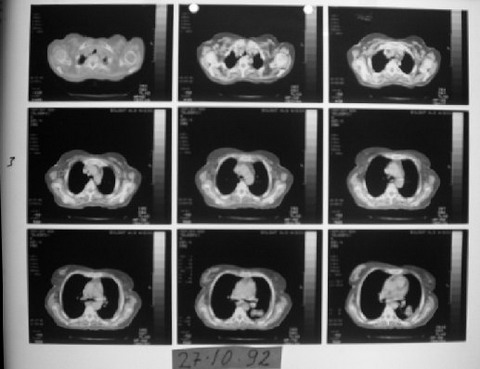

VAKA RAPORU- Teşhis: Maliyn lenfoma, akciğer kanseri - MG

EK MG3

27 Ekim 1992'de çekilen bilgisayarlı tomografi ve değerlendirme raporu.